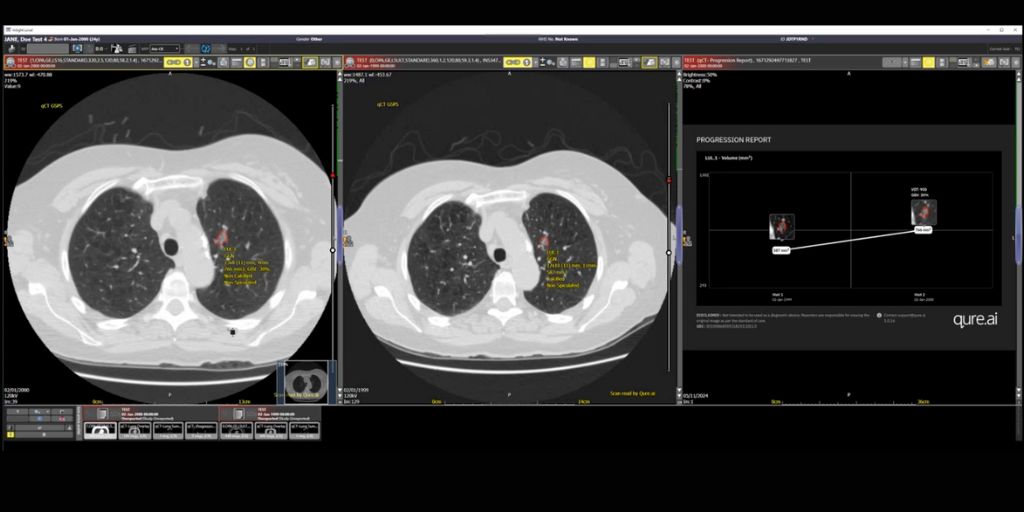

Tej Pandher, a Consultant Radiologist at University Hospitals Plymouth NHS Trust states, “Lung nodule AI assistance helps to identify and track suspicious nodules over time. The reporting radiologist can then put any such nodules into a clinical context and provide useful information for further follow up and/or treatment.”

“qCT has been designed to provide clinical decision support in the detection, characterisation, quantification and monitoring of lung nodules. It can also pull patient images from prior examinations to provide comprehensive nodule management and support progression monitoring over time. This makes it easier for the clinician to assess the growth of nodules with standardised data for volumetry assessment and an auto assigned malignancy risk score of pulmonary nodules using the Brock model/ BTS Guidelines,” continues Surabhi Srivastava.

qCT from global healthcare AI innovator Qure.ai, is part of an end-to-end AI-powered lung cancer care continuum suite of solutions for chest X-ray and CT, to detect, measure and track lung nodules.